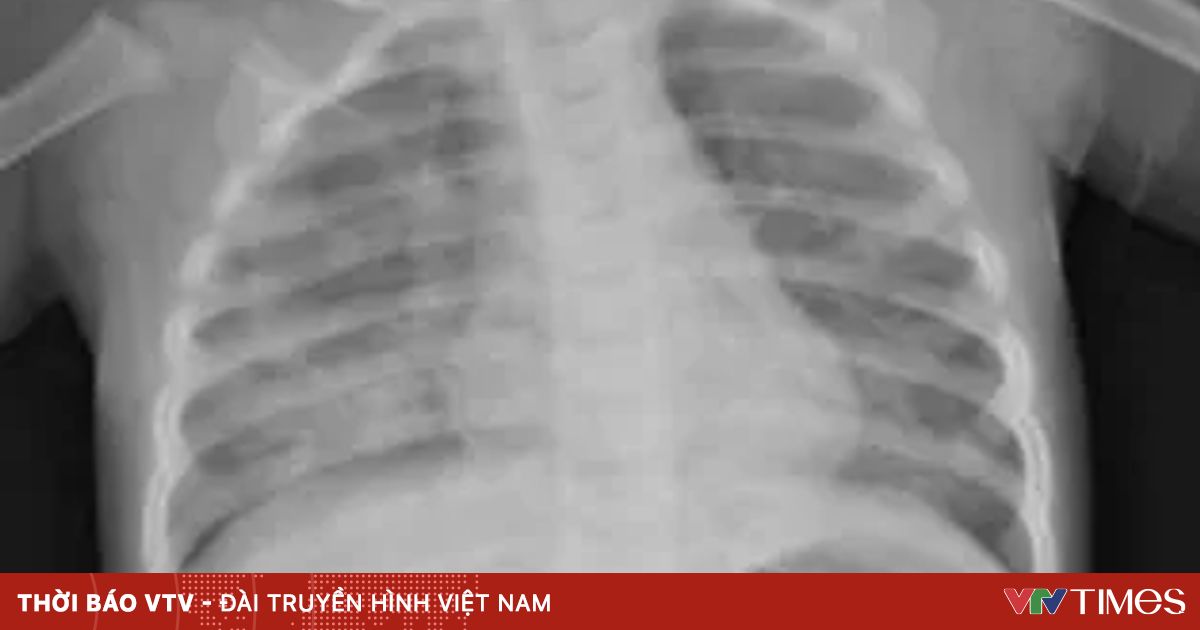

Tại đây, bệnh nhi có biểu hiện khó thở, tím tái, thở rút lõm ngực nặng, nhịp tim 180 – 200 lần/phút. Bệnh nhi được đặt nội khí quản giúp thở, kháng sinh, dịch truyền, điều chỉnh điện giải toan kiềm, an thần, giãn cơ, đặt ống thông dạ dày dẫn lưu hóa chất còn sót lại trong đường tiêu hóa ra ngoài.